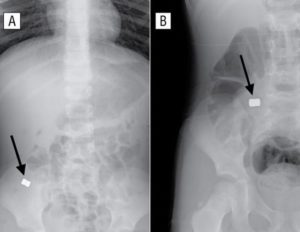

- Если проблем с дыханием нет, то ни в коем случае не нужно делать эти манипуляции с похлопываниями. Вы можете нанести травму, если будете делать их.Вместо этого лучше сделайте рентген, чтобы определить точное местонахождение инородного предмета, по необходимости — УЗИ.

Что малышу предстоит в больнице, если проглоченный предмет не вышел естественным путем? Первое, что должен сделать врач — отправить малыша на рентген. По результатам этой процедуры и будет решаться его судьба.

Если ребёнок проглотил мелкую пластмассовую деталь, которая беспрепятственно прошла по пищеводу, паниковать не нужно. Скорее всего, она выйдет самостоятельно через некоторое время. Даже при проведении рентгеновского обследовании рассмотреть её все равно не удастся из-за специфической структуры материала.